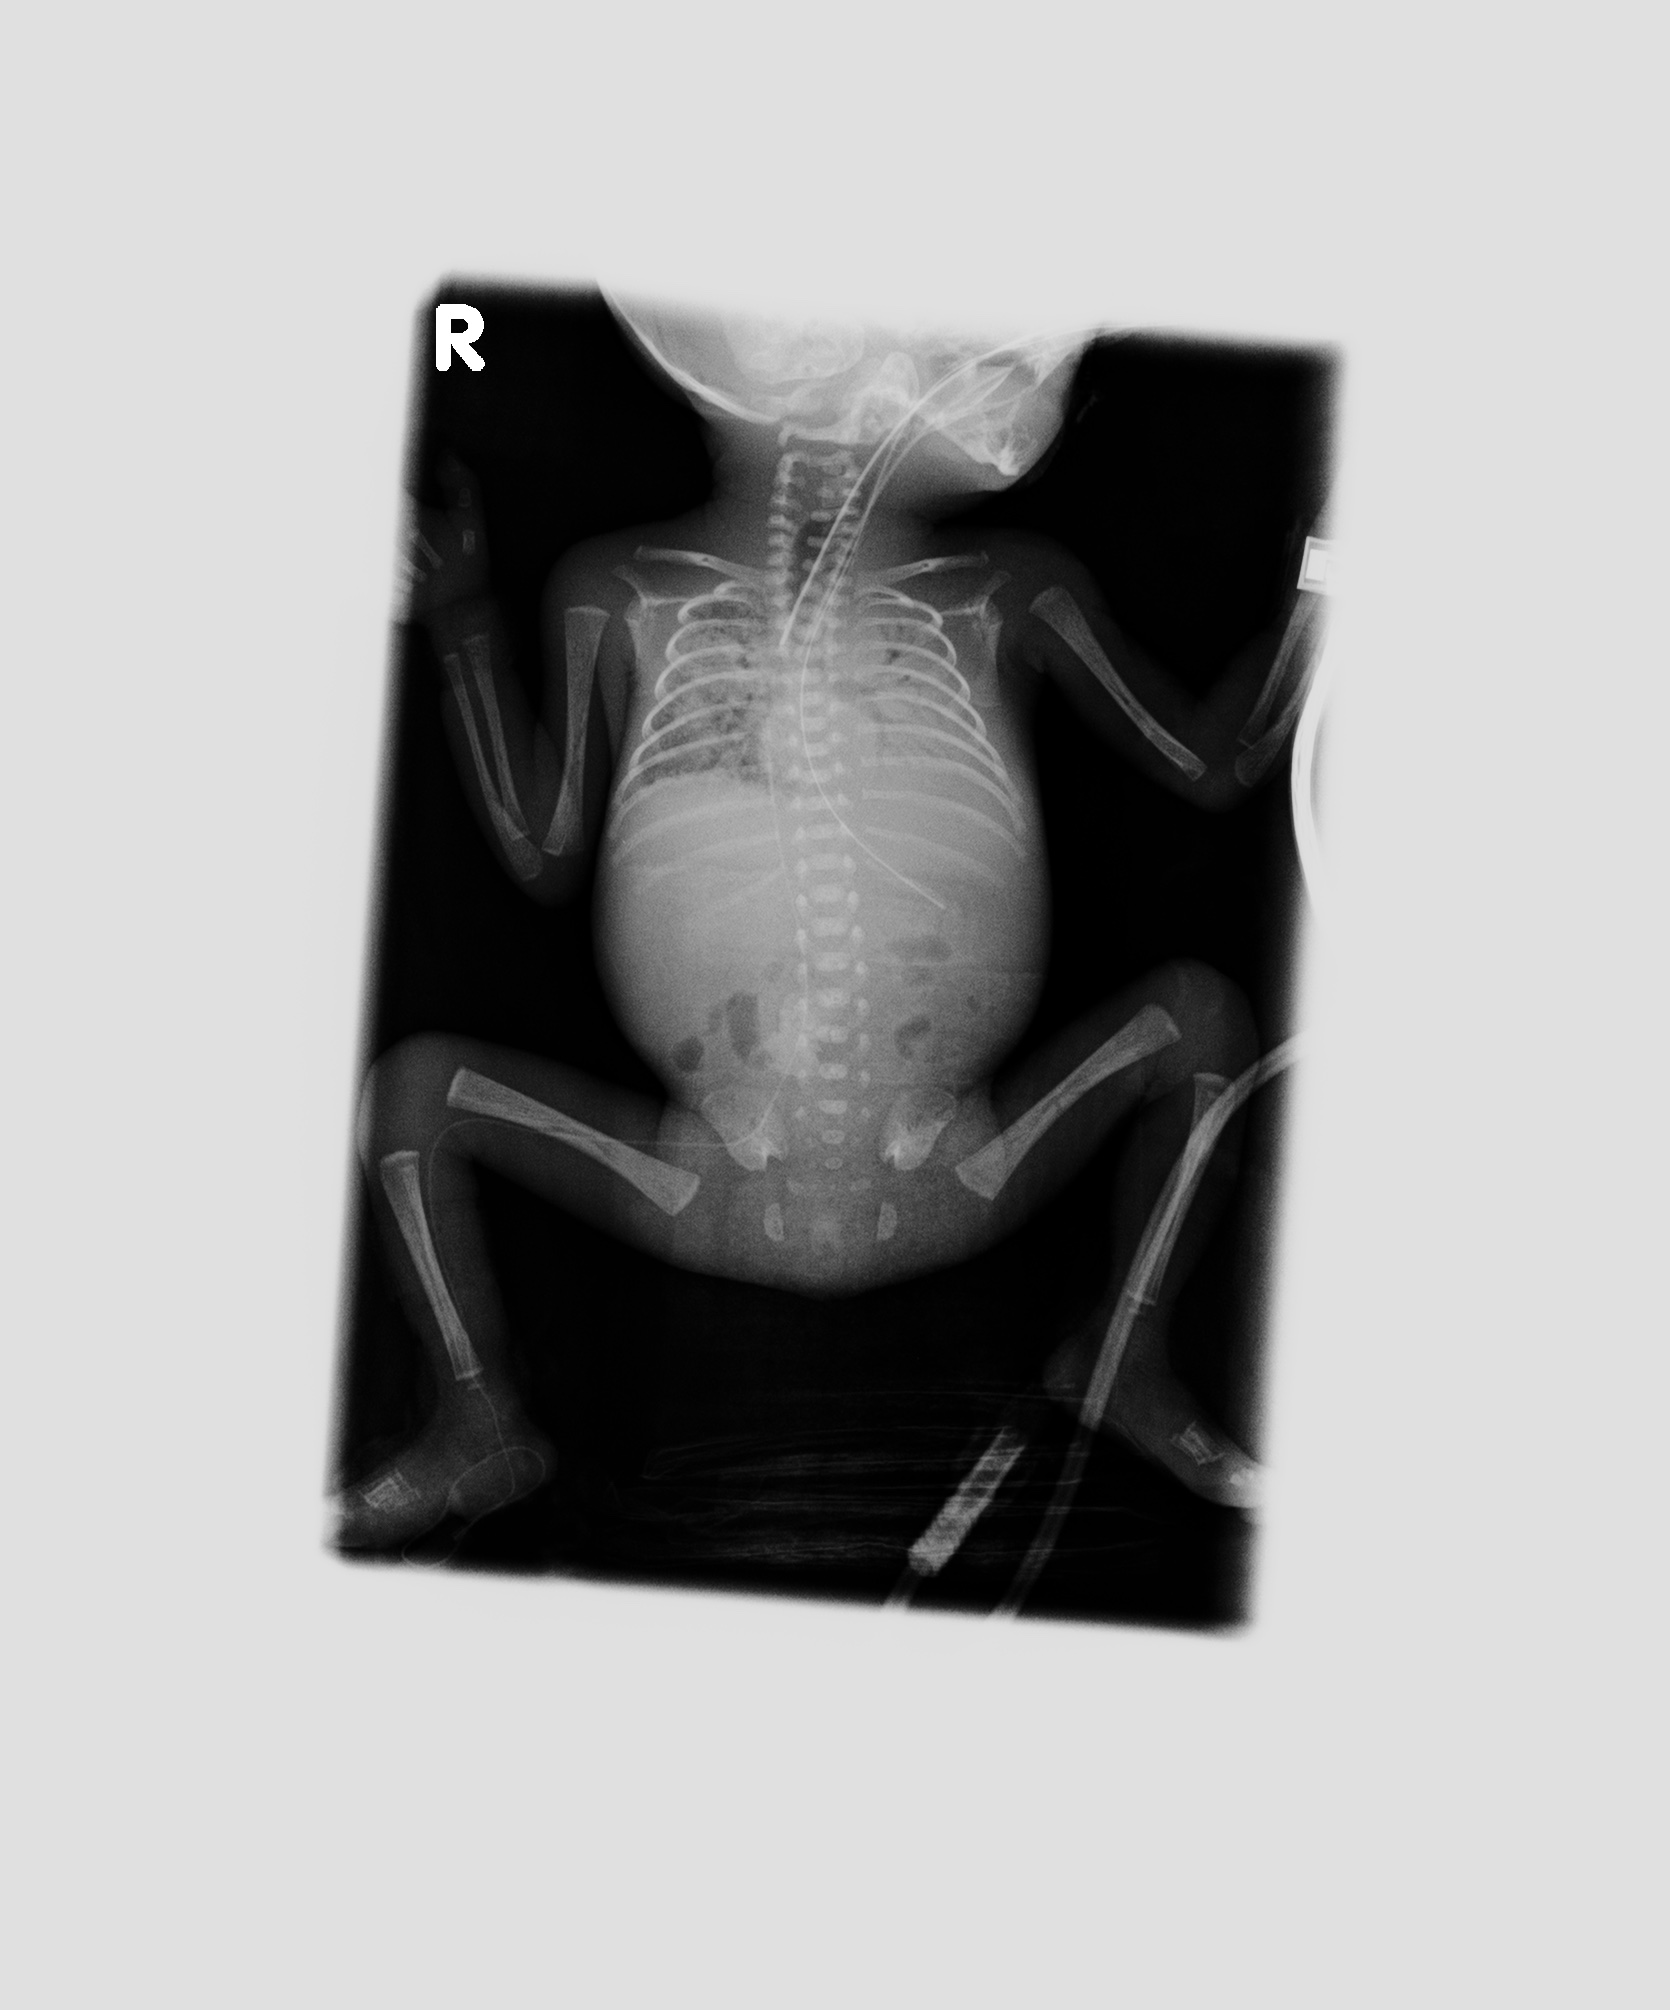

• (生前:○月24日13時44分、X線撮影)サーファクタント投与前の撮影と思われる。両側肺の volume 低下、透過性低下があり、RDS の状態にあると思われる。上腕骨の骨端線の骨濃度が骨幹部と不釣り合いに高く見える。非特異的所見ではあるが、すでに胎内で一定期間の侵襲が加わっていたことを示唆する。 この時点では carina での左右主気管支の分岐角は大きくなく、その後の撮影と対照をなす。この後心拡大が進行していったことを示している。

• (生前:○月25日10時19分、X線撮影)サーファクタント投与後の撮影と思われる。右肺は一定の含気が得られたが、肺野には微細な粒状影が蜜に分布し、依然として RDS 相当の状態にあると推測させる。 左肺はより末梢肺の拡張が不良で white out している状態。気管支の断面が大きく陽圧呼吸下にあることを示すが、空気漏出は生じていない。 気管内チューブ、右下肢からの PI カテーテル、胃管などのデバイス類の走行経路には異常なし。

• (生前:○月25日22時52分、X線撮影)右肺は前日より伸展し、air entry が得られている。肺紋理の血管断面が、いわゆる white dots として増強しており、肺の高血流状態を示す。左肺の air entry は昨日よりは良くなっているが、上葉の一部に留まっており右に比べて含気不良である。

• (生前:○月26日11時20分、X線撮影)両側肺は透過性が前日より高まっているが、25 日 10:19 時点のような RG パターン様の微細粒状影があるように見える。

• (生前:○月26日11時20分、X線撮影)両側肺の含気低下進行。左肺はほとんど含気を失っている。右肺でも斑状影が癒合するように拡大している。臨床的に観察された肺出血の際の胸部所見としては整合する所見で ある。気管の断面は拡張しており、陽圧がかけられていることを示唆しているが、この時点でも明らかな気道系からの空気漏出はない。食道内の空気が頸部に見える。